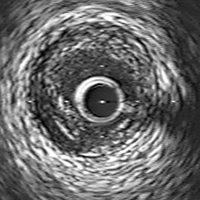

血管内イメージングにより近年注目をされている特殊病変に焦点をあてたImagingと進化を続けるPhysiologyのセッションです。